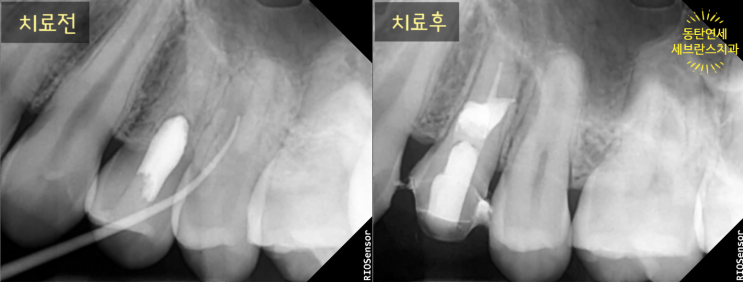

어렸을 때 잘못된 치외치 신경치료로 생긴 고름을 재신경치료로 해결

어린 22세 남자분입니다. (사실 22세면 다 큰 성인인데 이제는 뭐든지 다 도전할 수 있는 나이로 보이네요 ...